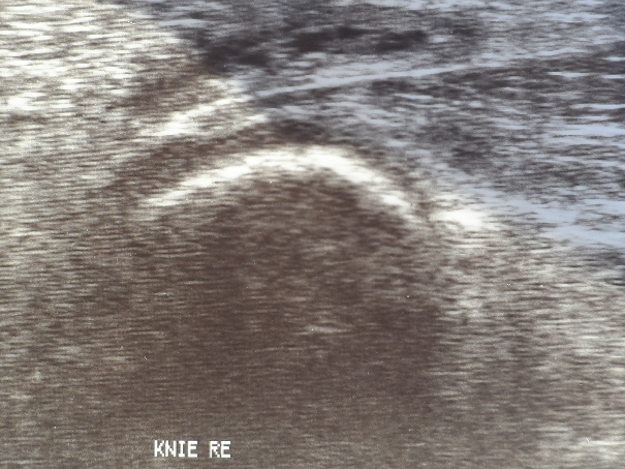

Sonographie (Ultraschall)

Als Ultraschall werden Schwingungen mit einer Frequenz oberhalb des Hörbereichs bezeichnet. In der Medizin wird in der Sonographie (Sonografie) Ultraschall als bildgebendes Verfahren zur Untersuchung von organischem Gewebe eingesetzt. Ultraschallwellen werden an den verschiedenen Geweben im Körper unterschiedlich stark zurückgeworfen (reflektiert). Das Ultraschallgerät sendet Ultraschallwellen aus, misst deren unterschiedliche Reflexion im Gewebe und verarbeitet sie in Echtzeit zu einem zweidimensionalen Bild des Körpers in unterschiedlichen Graustufen.

Die Ultraschall-Untersuchung kann aufgrund der unschädlichen Schallwellen auch bei Schwangeren und Kindern problemlos eingesetzt werden. Die Sonographie ist ein wichtiges Verfahren in der Schwangerschaftsvorsorge. Sie wird auch eingesetzt zur Untersuchung der weiblichen Brust, zur Untersuchung des Halses einschließlich der Schilddrüse und für die Beurteilung der Organe im Ober- und Unterbauch. Schlecht untersuchbar sind hingegen alle gashaltigen oder von Knochen bedeckten Organe.